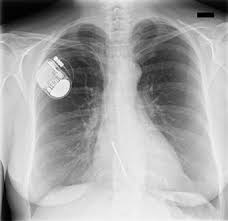

Herzrhythmusstorungen Komplett Subkutaner Icd Erfullt Die Anforderungen Springermedizin De

Herzrhythmusstorungen Komplett Subkutaner Icd Erfullt Die Anforderungen Springermedizin De from media.springernature.com